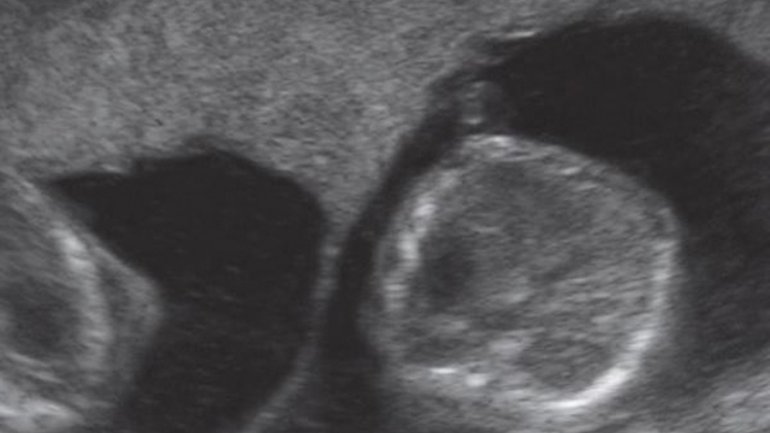

Ultraschall 5. SSW

Rechts im Bild ist die Fruchthöhle (schwarz) zu sehen. Der Embryo ist jetzt etwa zwei Millimeter lang und auf dem Ultraschall zu dieser Zeit oft noch nicht zu erkennen. Trotzdem beginnt in dieser Woche das Herz des Embryos zu schlagen.